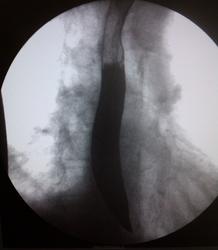

Пациент, 59 лет. Направительный диагноз: заболевание желудка? Жалобы на боли в эпигастрии, слабость, снижение памяти, отсутствие аппетита, одышку. Алкогольная зависимость 2 ст. На ФГДС: полип в верхнем трети тела желудка.. Какие будут мнения?

Что-то мне свод желудка не нравится

Да, какой-то он деформированный, хотя на 5 снимке вроде расправляется при раздувании, наверное складки такой эффект дают. А на 3-ем наверное тот полип

Обратила внимание, но этот дефект не получил подтверждения на других снимках. Чужие рентгенограммы ЖКТ, без скопии, оценивать очень опасаюсь. Не хватает именно функции, моторики.

Есть изменения антрального отдела. Как с перистальтикой?

Свод желудка типичное не то, на всех снимках есть патологические изменения. На ФГДС могли просто недостаточно исследовать этот отдел